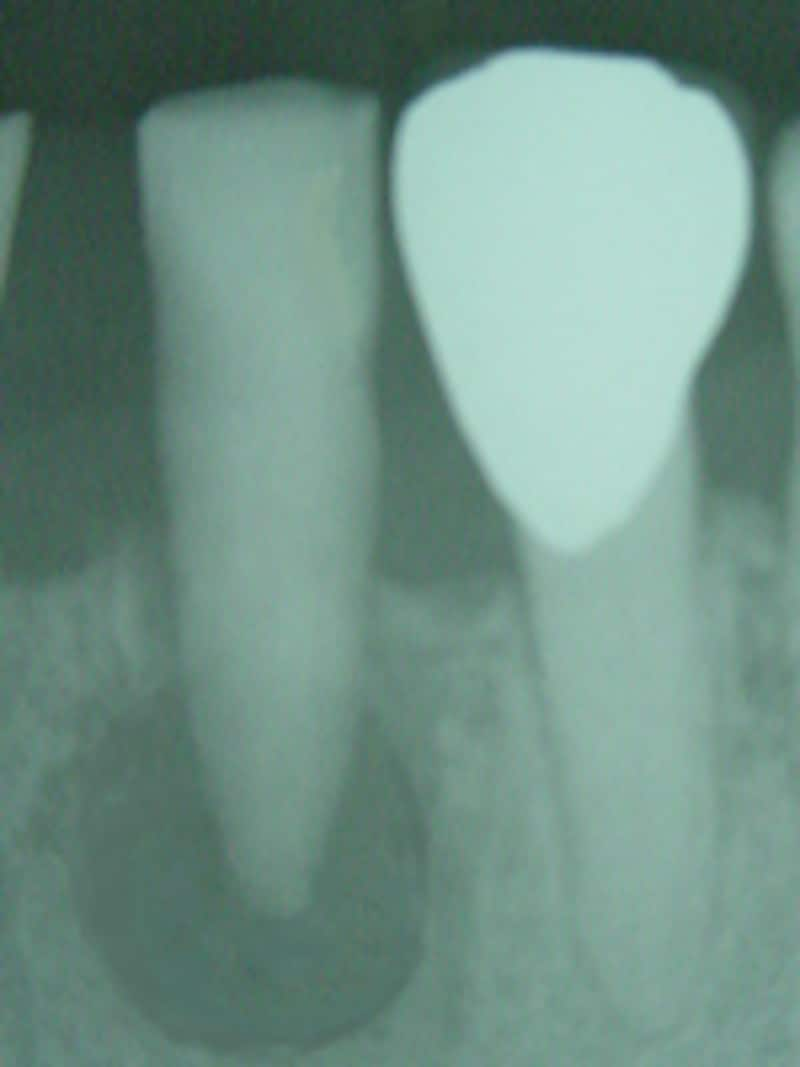

![]() |

| 骨を溶かし、内部に膿を溜め込んでいることもあります |